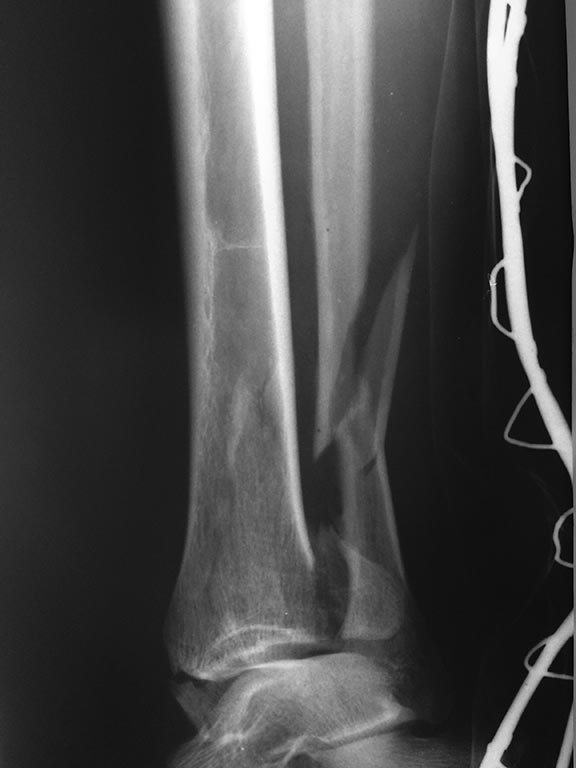

Травма голеностопного сустава 44С3 помогите определиться с оперативной тактикой

Пациентка 49 лет, повышенного питания, получила травму поскользнувшись на улице, сразу поступила к нам,

при поступлении наложен стержневой авф, прошло 5 суток, отек умеренный, будем готовы к пятнице к операции. Думаем 1/3 трубка на наружную, фиксация синдесмоза, вопрос в медиальной лодыжке и заднем крае, коллеги, подскажите какой фиксатор предпочтительнее, заранее благодарен, Дмитрий.

P.S: провести кт нет возможности и ни под каким углом(

С таким внутрисуставным характером перелом думаю лучше рассматривать как "пилон", а не "лодыжечный", т.е. 43С.

В данном случае повреждение межберцового синдесмоза выражается в отрыве заднего края б/б кости, восстановив который, вы компенсируете повреждение ДМС. Для восстановления метафиза с медиальной стороны лучше будет положить пластину (опорная, противоскользящая). Внутреннюю лодыжку можно винтами, можно по Веберу - это зависит от ваших ресурсов.

Все вместе это, тем не менее, перелом пилона, ближе к 43B1. КТ все-таки стоило бы изыскать возможность сделать. Лучше после наложения временного наружного фиксатора.

Классификация OTA/AO строится на морфологии повреждения, что определяет лечение, а не на механизме травмы. Который, конечно, довольно точно иногда может быть косвенно предположен. Скорее, надо спрашивать, почему возникает желание назвать это 44, если 44 - это переломы лодыжек. Да, здесь есть перелом внутренней лодыжки, но это же не все.

А здесь линия перелома tibia распространяется до границы с диафизом, если не выше, и связанной с диафизом остается только латеральная стенка дистального отдела tbia. То есть по характеру повреждения это никак не перелом лодыжек, а именно перелом пилона.

Соответственно, фиксация нужна не как при переломах лодыжек (треть трубки на малоберцовую+винт в задний край+спицы и проволока или винты во внутреннюю лодыжку), а как при переломе пилона - еще и опорная пластина на дистальный отдел tibia, или аппарат.